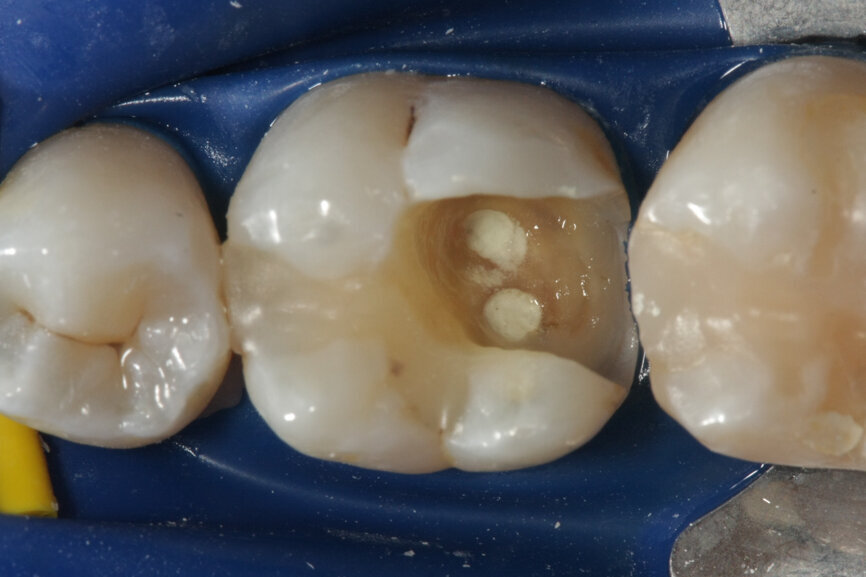

Vital pulp therapy has become more popular in recent years. Calcium hydroxide has been the most common material for pulp capping, but MTA has shown even better results in biocompatibility and outcome.[3] Cases with large carious pulp exposure can be treated successfully with partial pulpotomy and MTA as a capping agent, keeping teeth vital (Figs. 1a–e).

Fig. 1a: (a) Deep carious lesion. (b) Partial pulpotomy. (c) MTA application with the MAP System and PD MTA White. (d) Filling. (e) Post-op radiograph showing the pulp capping with MTA.

Fig. 1b: (a) Deep carious lesion. (b) Partial pulpotomy. (c) MTA application with the MAP System and PD MTA White. (d) Filling. (e) Post-op radiograph showing the pulp capping with MTA.

Fig. 1c: (a) Deep carious lesion. (b) Partial pulpotomy. (c) MTA application with the MAP System and PD MTA White. (d) Filling. (e) Post-op radiograph showing the pulp capping with MTA.

Fig. 1d: (a) Deep carious lesion. (b) Partial pulpotomy. (c) MTA application with the MAP System and PD MTA White. (d) Filling. (e) Post-op radiograph showing the pulp capping with MTA.

Fig. 1e: (a) Deep carious lesion. (b) Partial pulpotomy. (c) MTA application with the MAP System and PD MTA White. (d) Filling. (e) Post-op radiograph showing the pulp capping with MTA.